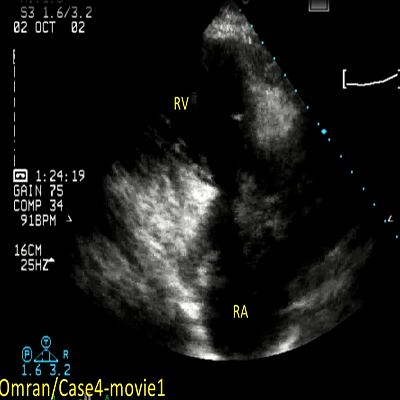

Rheumatic mitral stenosis

2 MB